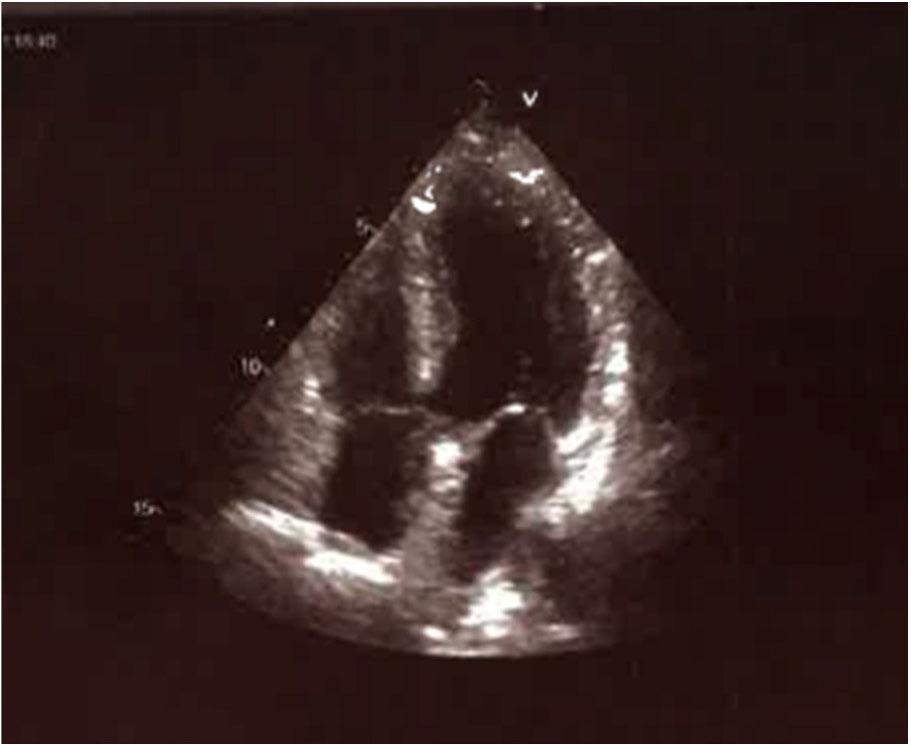

Figure 2.